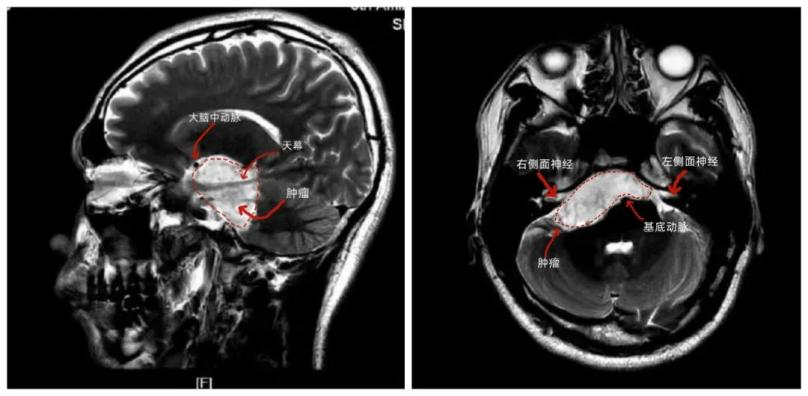

据神经外科刘飞主任介绍,患者的肿瘤主体位于右侧桥小脑角区并包裹多条神经血管、向上方跨过天幕长到中颅窝、跨过中线的基底动脉长到左侧。该区域涉及供应脑干血液的基底动脉和分支,还有负责听力、眼球运动、面部运动的各种神经。患者肿瘤较大,240度包绕脑干并挤压脑干移位,如不尽快手术,肿瘤将进一步压迫脑干,威胁生命。

手术前

考虑肿瘤涉及范围太广,涉及的血管神经太多,术后患者可能出现面瘫、听力受损等并发症,且常规显微手术难以全切肿瘤,如肿瘤残留不仅需要二次手术,患者术后可能会长时间发热,危及生命。刘飞主任手术团队根据术前影像资料,预估肿瘤性质后,制定了周密的手术计划: